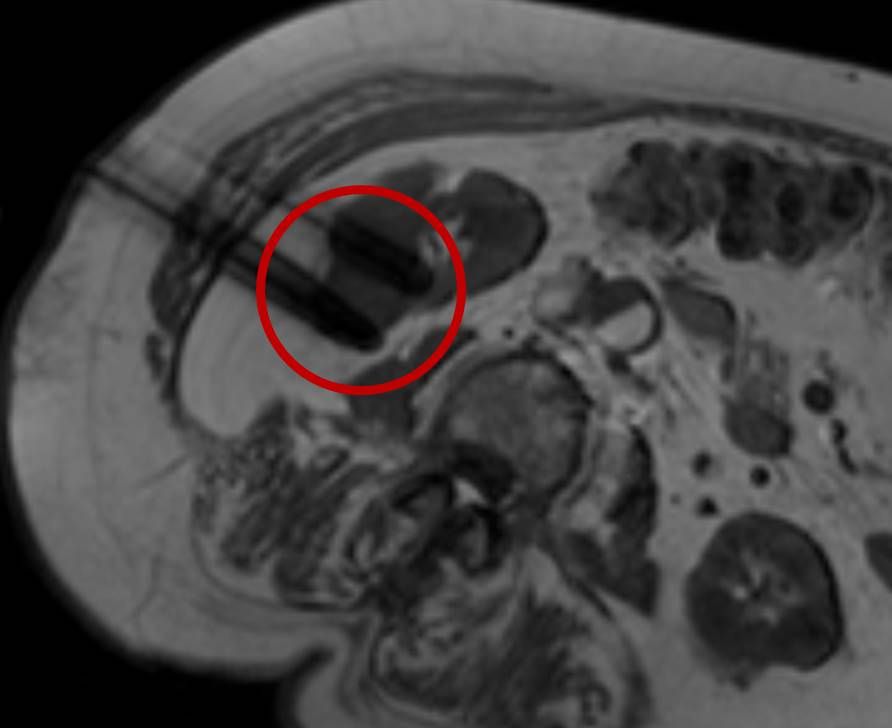

Thermoablation von Nierentumoren

Die minimalinvasive Thermoablation ist auch eine Therapieoption für bestimmte Nierentumore. Damit ein Nierentumor mit einem thermoablativen Verfahren (Radiofrequenzablation oder Mikrowellenablation) effektiv und sicher behandelt werden kann, müssen bestimmte Bedingungen (wie Größe, Anzahl und Lage) erfüllt sein. Dies wird im Vorfeld des Eingriffes mit Kollegen der Urologie besprochen.

Bei der perkutanen Thermoablation von Nierentumoren werden spezielle Applikatoren unter CT- oder MRT Bildgebung in den Zieltumor eingebracht. Durch Hitze wird der Tumor zerstört.